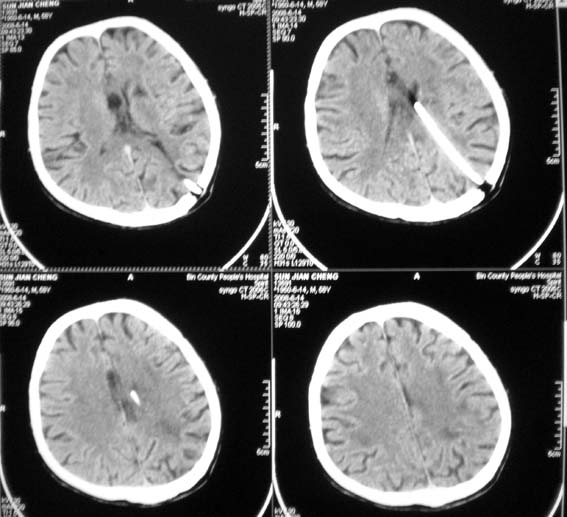

以下是引用随光逐影在2008-6-15 17:27:00的发言:[br]1)脑积水引流术后导管留置。2)蛛网膜下腔出血。3)左侧基底节区及左侧额叶多发脑腔隙灶。4)脑萎缩。